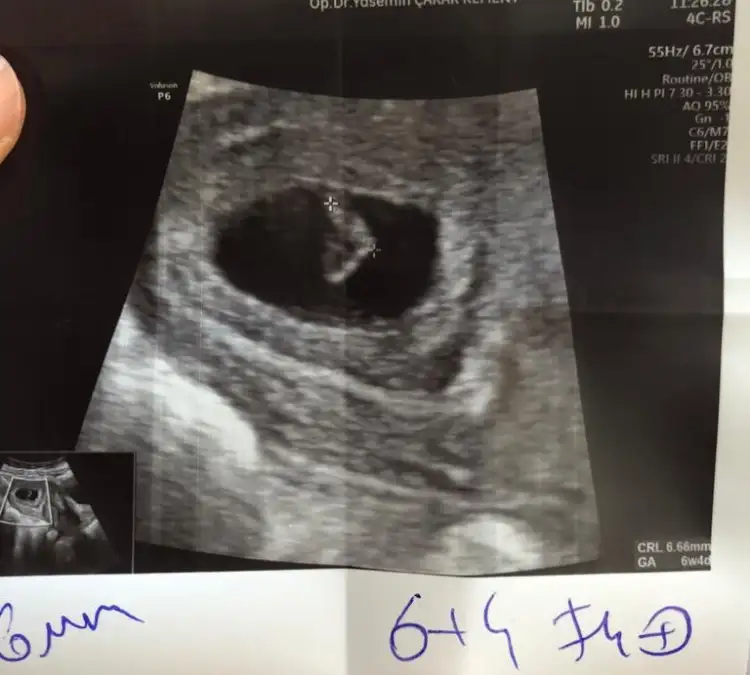

8+4 karından ultrasonla. Rica etsem tahminde bulunur musunuz? 🥰

IMG_20210112_102649.webp

Anlaşılıyo mu ya çok minik :)